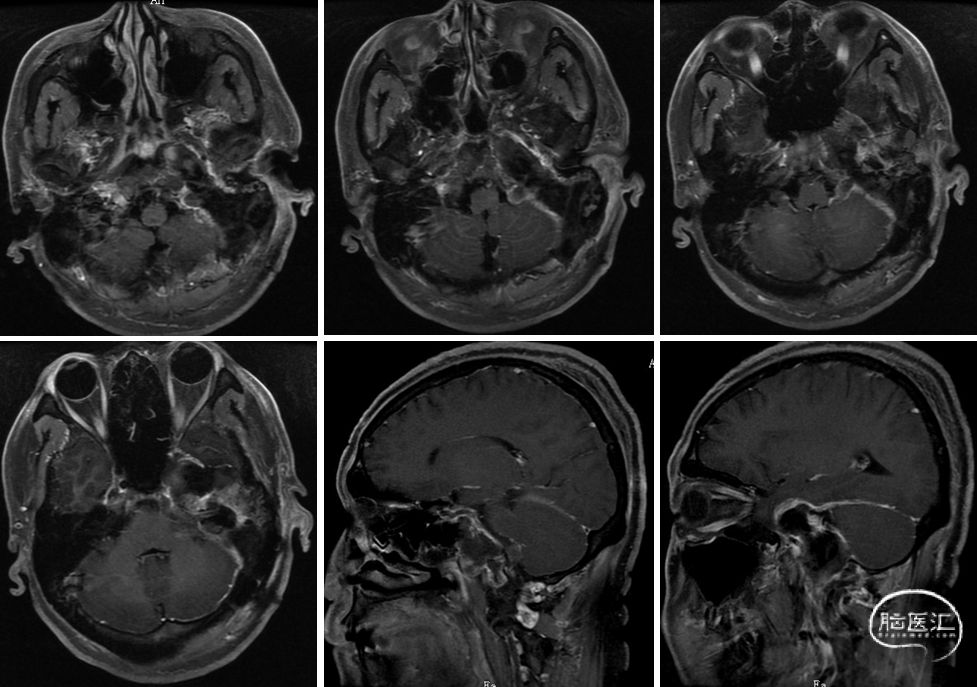

术前影像

术后影像

术后MRI提示肿瘤切除满意